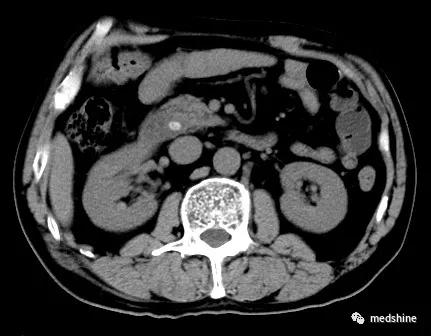

部分胆囊结石患者合并胆总结石,如果术前或术中没有发现胆管结石单纯实施了胆囊切除手术,就会导致胆总管残余结石,术后可能会出现相应的问题。还有少数患者在胆囊切除多年以后新发胆总管结石。

胆总管结石

对于胆总管结石,如果大于3.5mm,不论有无症状,一旦发现都应进行治疗。目前主要有内镜下oddi括约肌切开取石和腹腔镜联合胆道镜手术取石两种方法,应根据具体情况合理选择 。